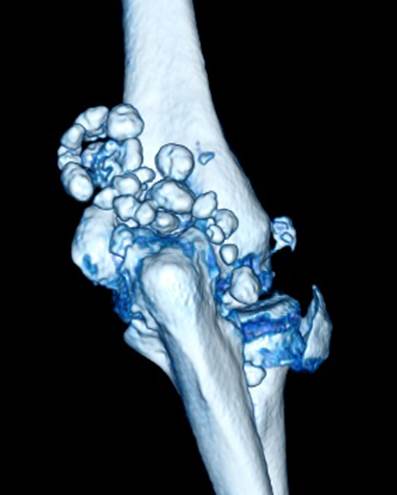

肘关节滑膜软骨瘤病

肘关节镜治疗滑膜软骨瘤病